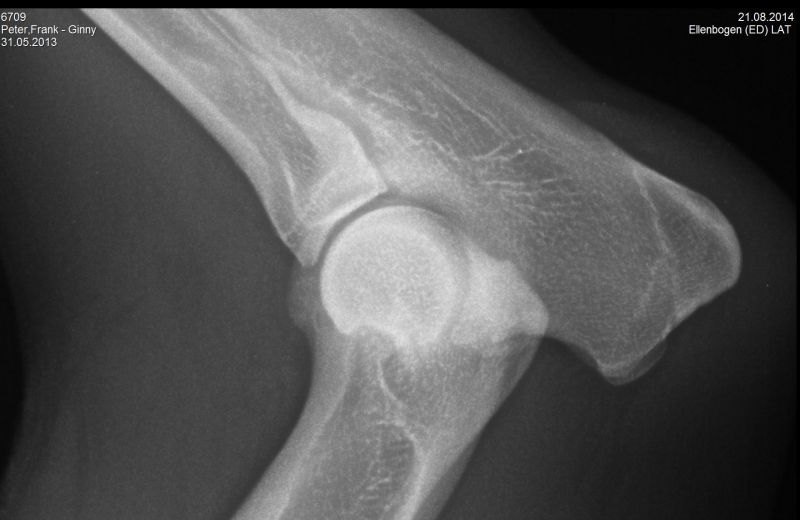

21.08.2014 - Ginny HD-und ED geröntgt - 15 Monate alt

24.08.2014 - Ginny - 15 Monate alt